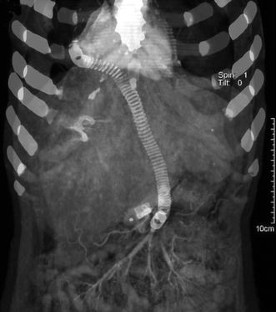

Fig. 1